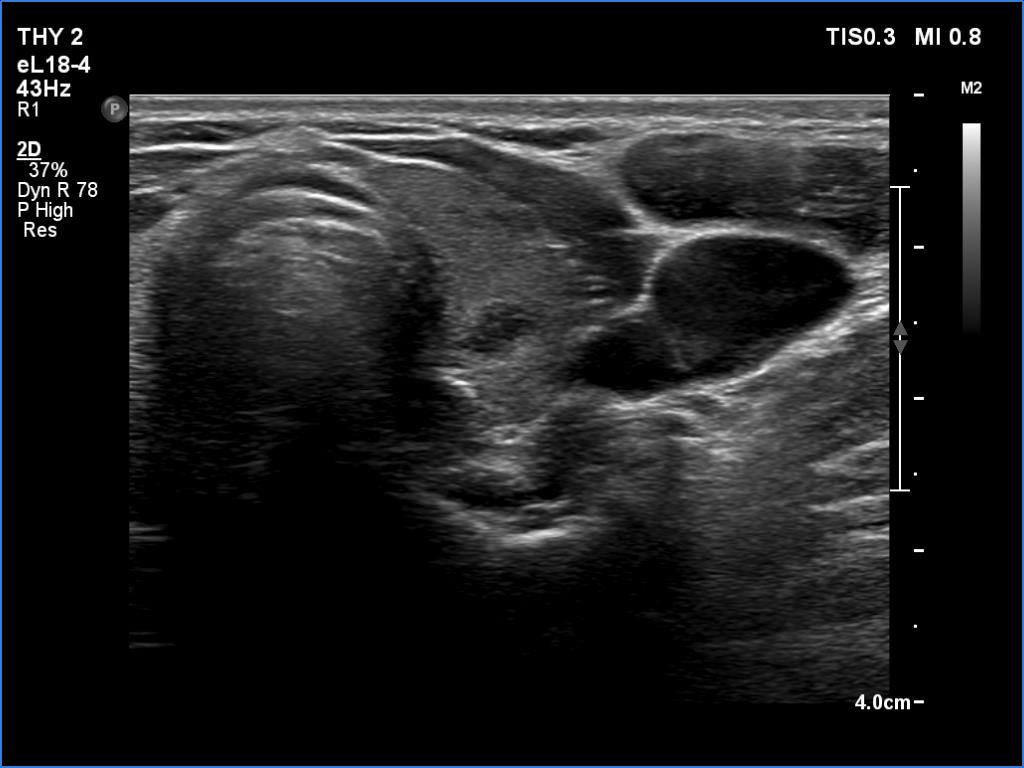

Ultrasonography. The thyroid was minimally hypoechoic and had several deeply hypoechoic discrete lesions. The latter had irregular margins and corresponded to more active foci of thyroiditis.